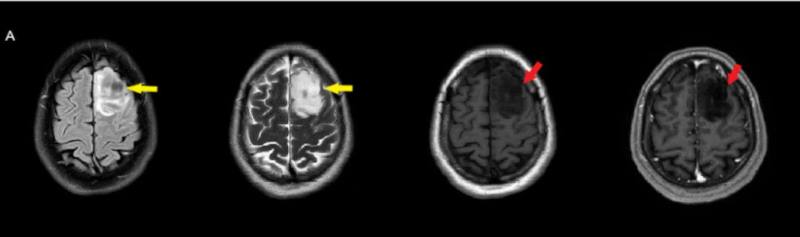

- Sol frontal kortikal-subkortikal yerleşimli aksiyel T2A görüntüde hiperintens sinyal özelliği gösteren (oklar) ve FLAIR görüntüde sinyali ağırlıklı olarak baskılanan (oklar) kitlesel lezyon izleniyor. Lezyon T1A görüntüde hipointens olup post-kontrast T1A görüntüde bu düzeyde patolojik kontrastlanma izlenmiyor (oklar).

- ADC görüntülerde lezyonda sinyal artışları ile karakterize difüzyon artışı (ok) izleniyor. Bu alana yönelik yapılan multivoksel MR spektroskopi incelemesinde (ok) kolin pikinde artış ve NAA pikinde azalma izleniyor. Cho/Cr oranı 1.76 ölçülüyor.

- FLAIR’de T2’ye benzer şekilde hiperintens görünür. Ancak T2–FLAIR mismatch bulgusu, bu tümör tipi için oldukça karakteristiktir.

- T2–FLAIR mismatch bulgusu, T2AG’de homojen hiperintensite ile FLAIR görüntüde santral sinyal baskılanmasının ve çevrede hiperintens halka görünümünün bulunduğu bir fenomendir. Bu bulgu, özellikle IDH-mutant, 1p/19q kodelesyonu olmayan astrositomları tanımlamada oldukça özgül bir biomarker olarak literatürde vurgulanmıştır. Ayırıcı tanıda akla gelmesi gereken oligodendrogliomlarda T2/FLAIR mismatch bulgusu genellikle görülmez.

- Olgumuzda T2-FLAIR mismatch bulgusu mevcut olup, opere edilmiş ve tanısı histopatolojik olarak konulmuştur.